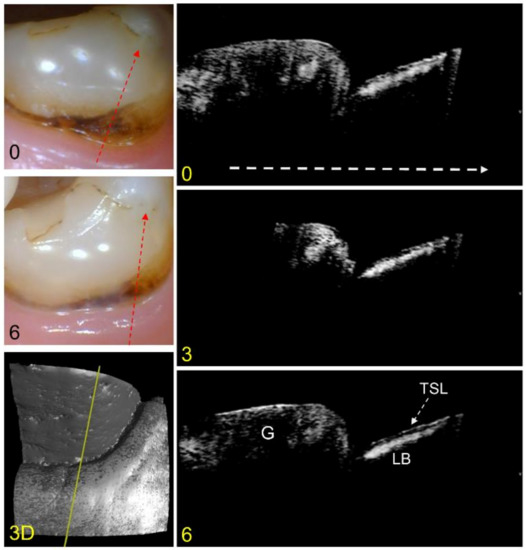

An example of an arrested lesion with minimal change after 6 months is shown in the color and CP-OCT images of Figure 2. In the color images, the lesion area looks similar, however, the exposed root surface appears to have decreased due to growth of the gingival margin. A surface rendering (3D) of the entire CP-OCT scan taken at the baseline is also shown, with the yellow line showing the position of the extracted CP-OCT b-scans. The CP-OCT scan at the baseline shows the gingiva on the left and the exposed root surface on the right. The lesion appears with a lesion body of higher intensity covered by a thin transparent layer (dark zone) that indicates the TSL. The TSL has a very thin layer of higher intensity that represents reflectance from the tooth surface. The lesion does not appear to change in depth or severity after 6 months.

Figure 2.

Color pictures at baseline and 6 months are shown for an arrested lesion. The dashed red lines show the likely position of the three CP-OCT b-scans shown at baseline, 3 months, and 6 months. The white dashed arrow in the OCT b-scan is directed from the root to the crown. A surface rendering (3D) of the entire CP-OCT scan taken at baseline is also shown, with the yellow line showing the position of the extracted b-scans. The position of the gingiva (G) and the lesion body (LB) with the TSL located on top of the lesion are indicated. Little change has occurred for the lesion over 6 months.